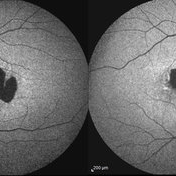

Central Areolar Choroidal Dystrophy Central Areolar Choroidal DystrophyJul 7 2015 by Hamid Ahmadieh, MD OCT images of both eyes of a 58-year-old man with progressive loss of vision. VA OD is 20/60 and VA OS is 20/400. Photographer: Soulmaz Shahmohammad, Negah Eye Center, Tehran, Iran Imaging device: Specteralis Condition/keywords: central areolar choroidal dystrophy (CACD), optical coherence tomography (OCT)